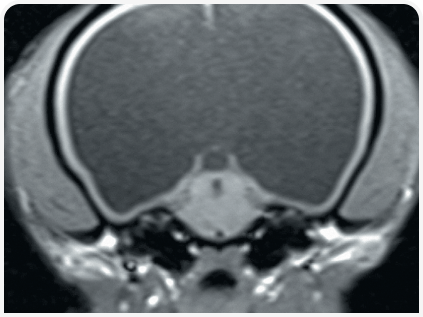

Диагноз ставится на основании изменения размера и формы черепа, неврологических признаков заболевания и нейровизуализации.

Практичным методом визуализации боковых желудочков является ультразвуковое исследование через открытый родничок.